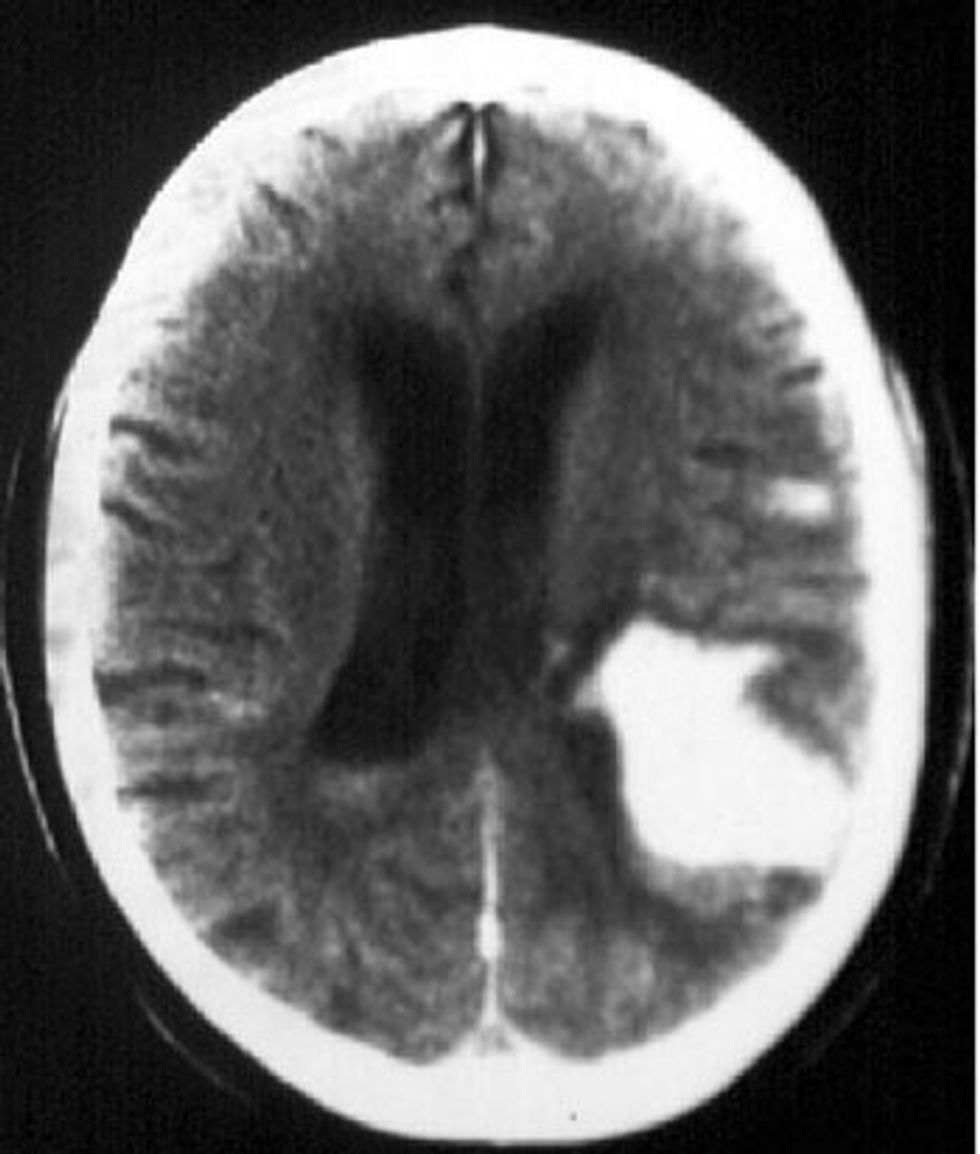

CT endocraniumi ku shihet hematoma intracerebrale Temporo – Occipitale e djathtë hyperdense me edem përreth hematomes si dhe shift i hemisferës së djathtë majtas ku shihet që ventrikujt në anën e djathtë, janë të komprimuar nga efekti mase i hematomes.

CT endocraniumi ku shihet hematoma intercerebrale me lokalizim kortikal dhe subkortikal parietal majtas në ditën e shtatë me fillim të resorbimit, që paraqitet me hipodensitet përreth hematomës